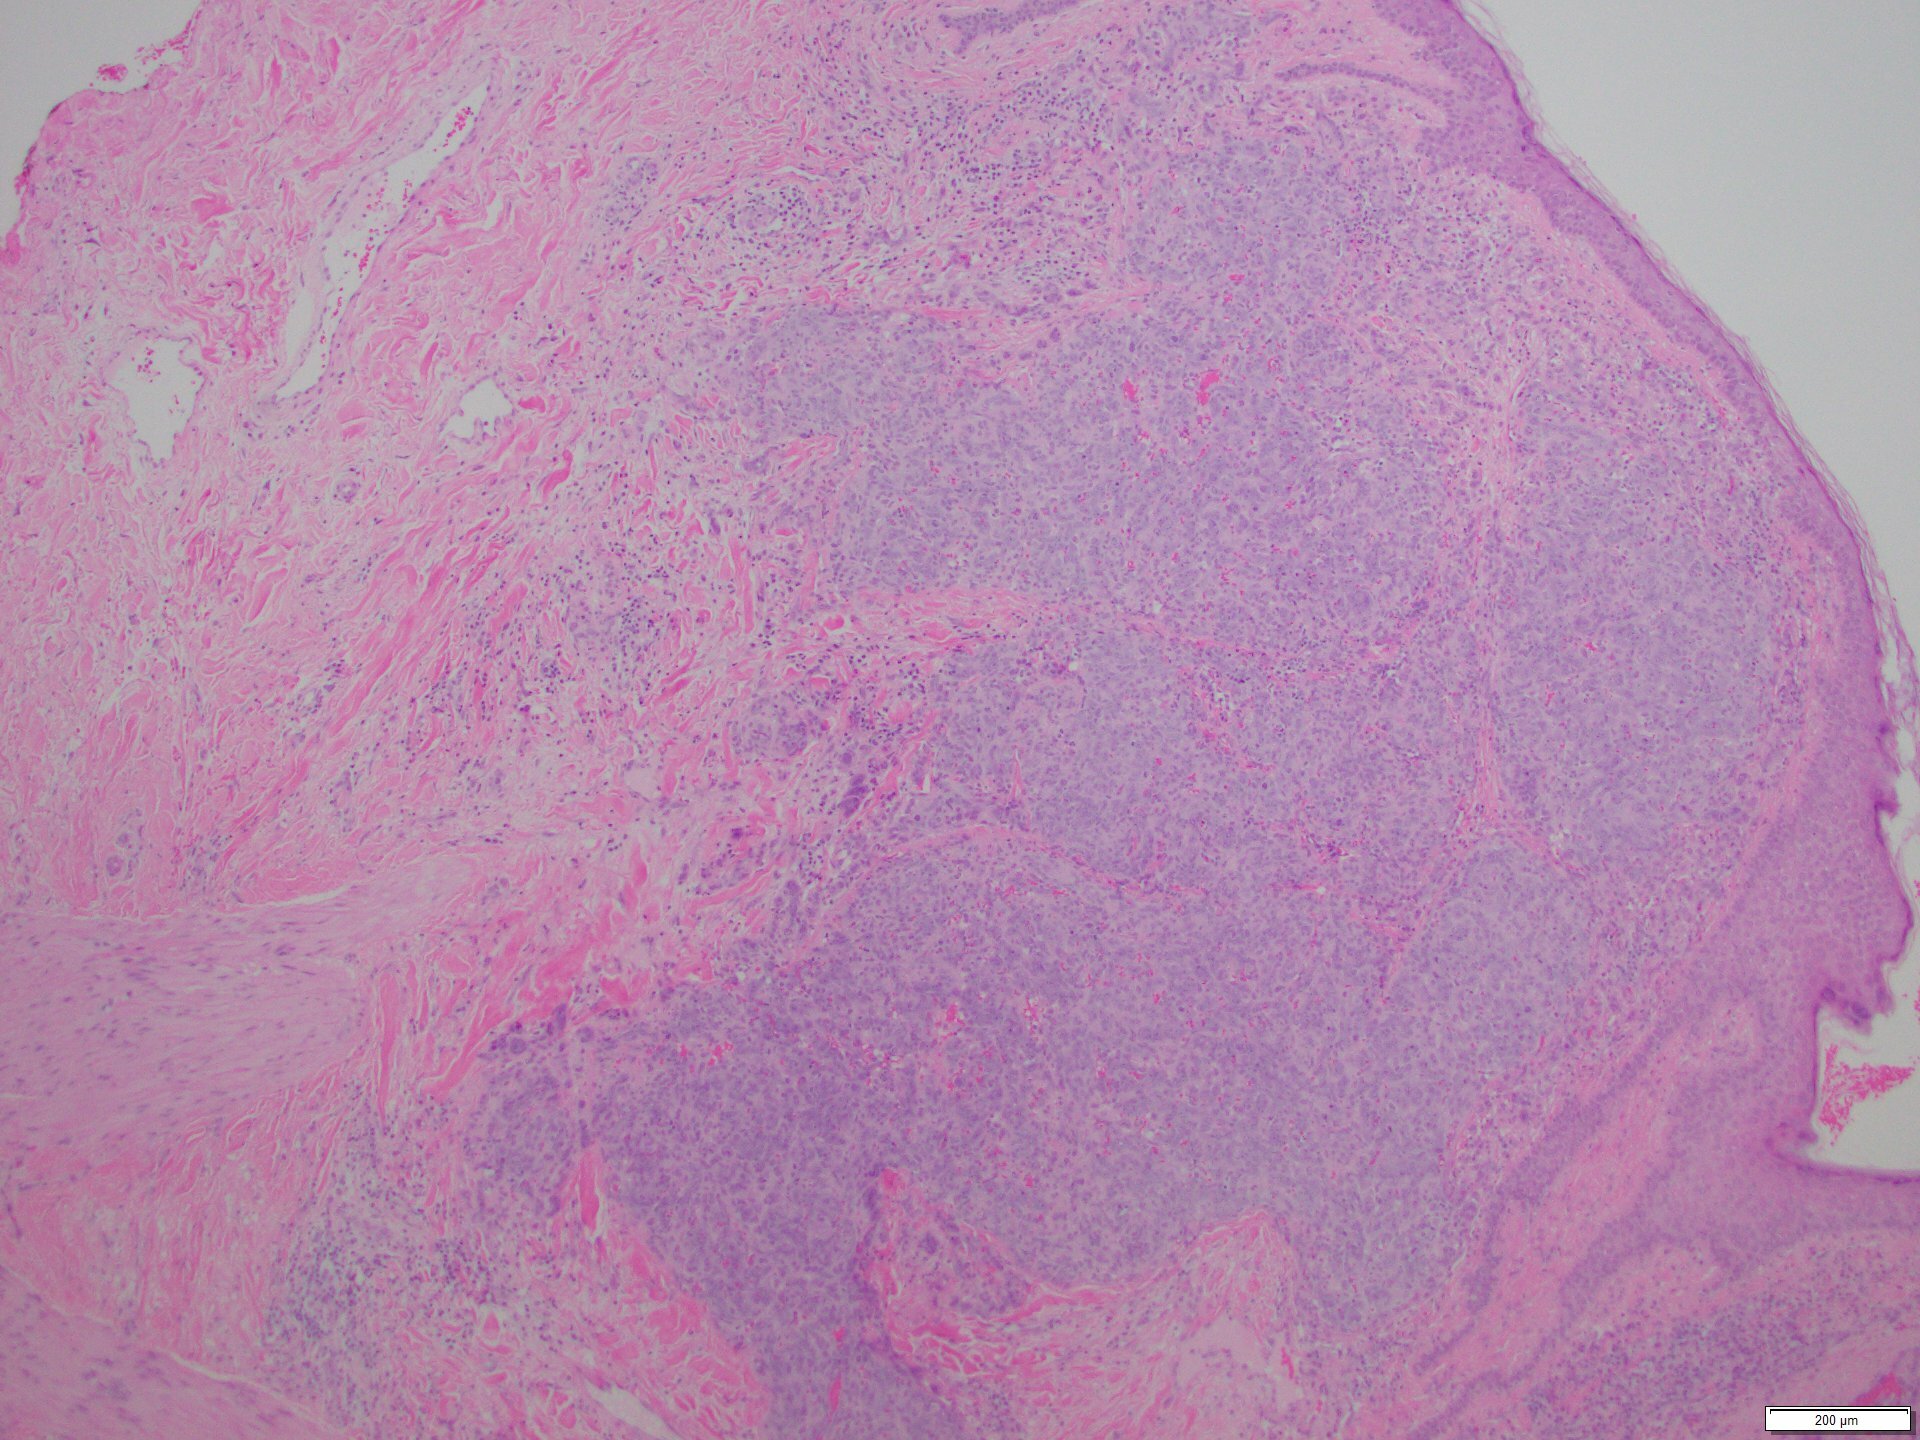

The skin lesion was completely excised and sent to pathology for diagnosis (Figures 1-3). The lesion is hypercellular with an infiltrative, predominantly solid, growth pattern in the dermis and subcutaneous tissue. It is highly vascular and has complex anastomosing and poorly formed vascular channels. The tumor cells are large, pleomorphic, have vesicular chromatin, and prominent nucleoli. There are frequent mitoses and extravasated red blood cells throughout. Immunohistochemistry shows the tumor cells are diffusely positive for ERG (Figure 4) and c-MYC (Figure 5) while negative for pan-cytokeratin (Figure 6) and GATA3. Subsequently, the patient underwent a left total mastectomy.